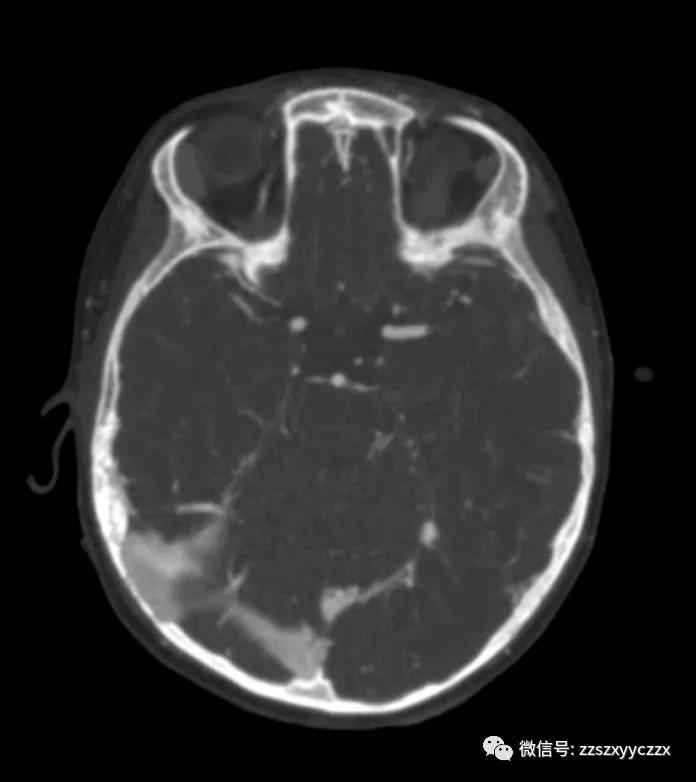

脑电图检查结果正常。脑计算机断层扫描(CT)显示没有急性缺血的证据(图1)。CTA显示左大脑中动脉M1段有血栓(图2)。该患者符合静脉注射重组组织型纤溶酶原激活剂(rtPA)治疗的所有标准纳入标准,包括血压参数、实验室研究和头部影像无颅内出血。在症状出现后3.5小时,静脉注射rtPA,剂量为0.9 mg/kg,总剂量的10%团注,其余90%在1小时内注射。rtPA灌注治疗完成且无并发症。在rtPA后1小时内,观察到他的右侧偏瘫和失语症有所改善,PedNIHSS评分为7分。

图1 非增强CT未显示实质性低密度灶